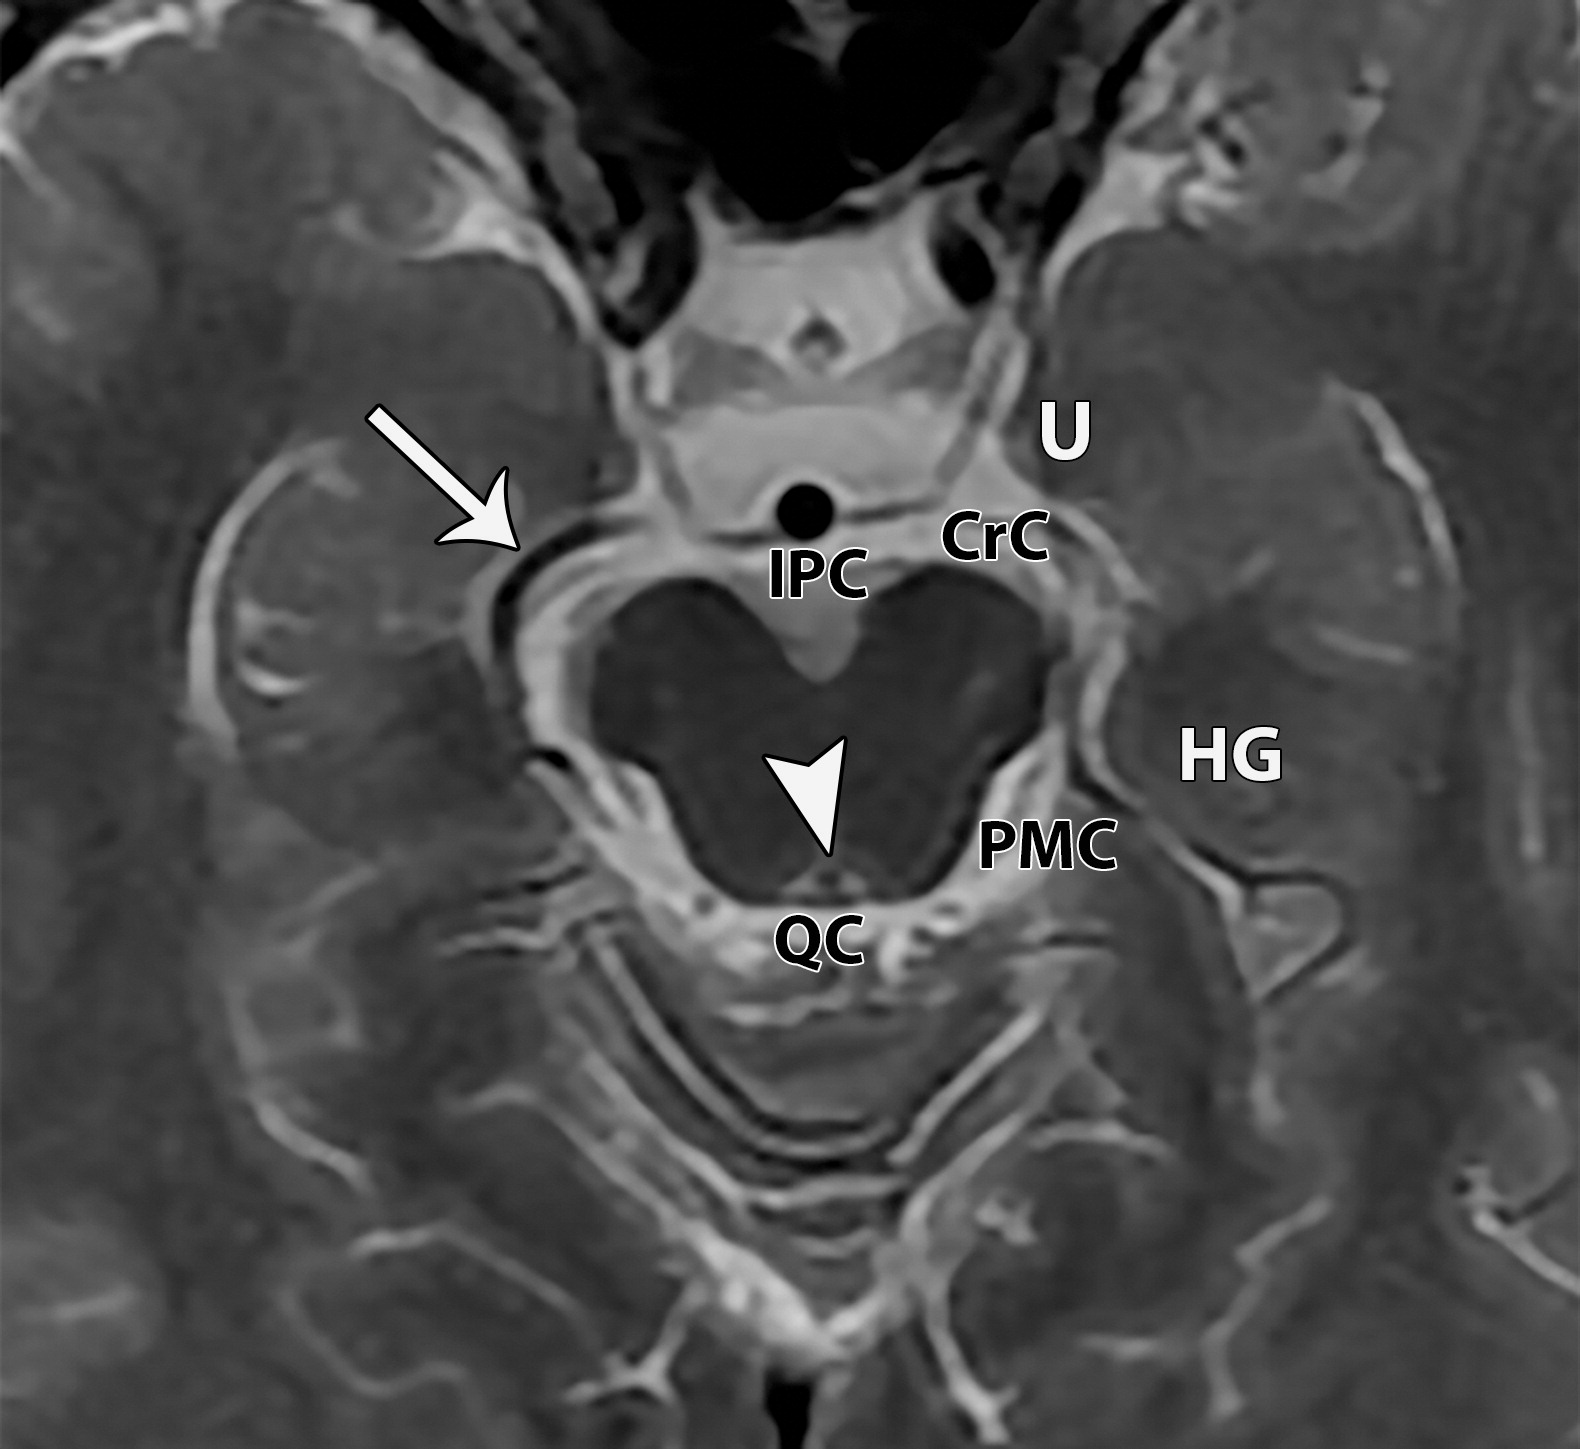

中脑导水管(白色短箭头),大脑后动脉(白色长箭头),大脑脚池(CrC),海马回(HG),大脑脚间池(IPC),中脑周围池(PMC),四叠体池(QC),钩回(U)。